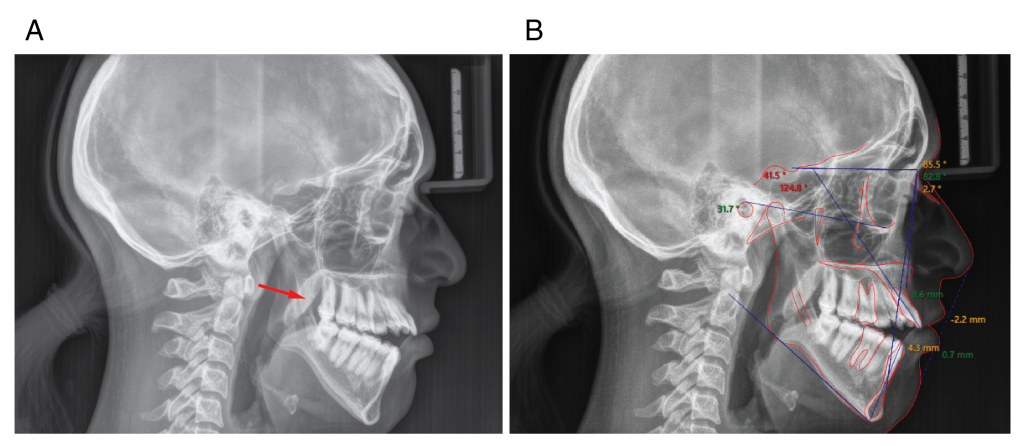

Figure 2: Lateral cephalogram of the patient with Nemaline Myopathy. (A) The patient demonstrated clockwise rotation of the mandible, which gives the patient a Class II skeletal relationship, increased mandibular plane angle, and increased lower facial height. The soft palate was very prominent (red arrow). (B) cephalometric tracing and analysis.

Table I: Cephalometric analysis of the patient with NM. Skeletal and dental measurements where completed on a Cephalogram obtained before initiation of treatment (deg= degrees, mm= milimeters).